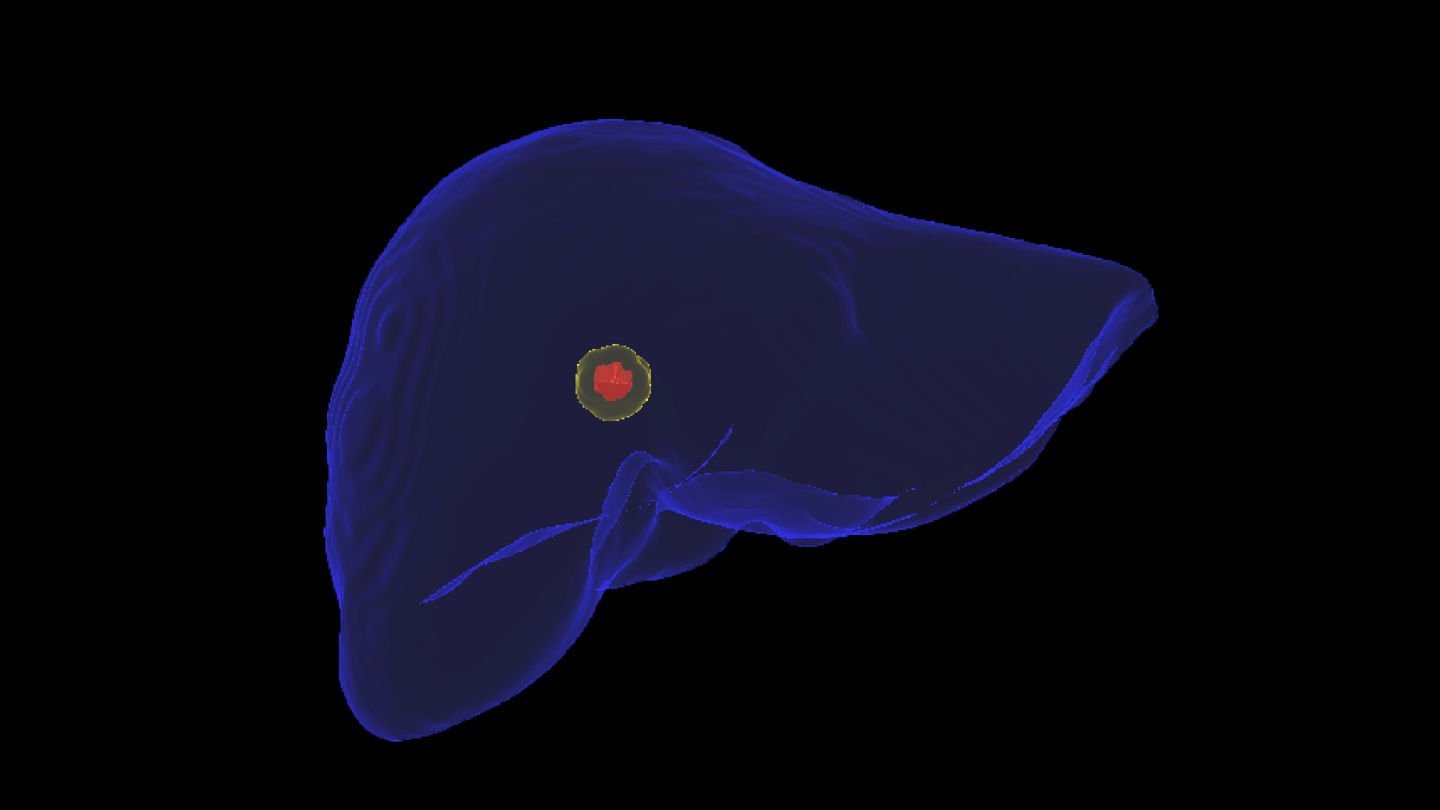

1. PLANNING

The Liver Ablation module offers tools for automatic segmentation of relevant structures. Combined with the ability to place virtual applicators and estimate the ablation zone, our software assists users to determine the optimal number of applicators and their precise placement.